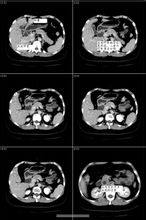

腹部X线平片、胆囊和胆道X线造影、腹部B超和腹部CT检查、内镜逆行胰胆管造影(ERCP)和经皮肝穿刺胆道造影(PTC),均有助于阻塞性黄疸的定性和定位诊断。 - 治疗用药